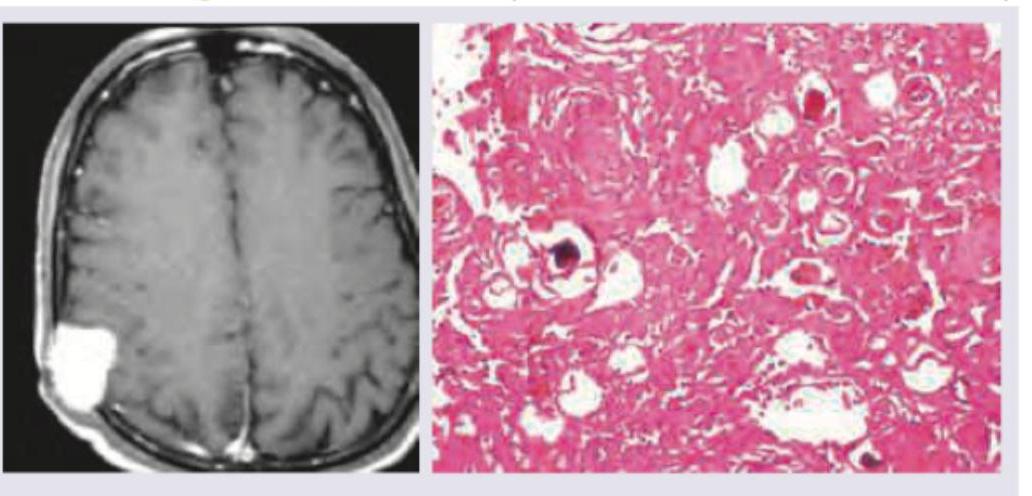

Question 1: A 50-year-old woman presents with daily early morning frontal headache and projectile vomiting. The image shows:

- D. Meningioma (Correct Answer)

Explanation: **Meningioma** - The MRI shows a **well-circumscribed, extra-axial mass** that is significantly enhancing, particularly in the frontal lobe near the convexity. Histopathology of a meningioma characteristically features **whorls of meningothelial cells** and **psammoma bodies** (calcified concentric lamellae), which are visible in the image. - The clinical symptoms of **early morning headaches** and **projectile vomiting** are indicative of **increased intracranial pressure**, which can be caused by any space-occupying lesion, including a meningioma, especially if it grows to a significant size. *Medulloblastoma* - This is a highly malignant brain tumor typically occurring in the **cerebellum of children**, not usually seen in a 50-year-old woman in the frontal lobe. - Histologically, medulloblastomas are composed of small, round, **blue cells** with little cytoplasm (small blue cell tumor), which is distinct from the provided image. *Glioma* - **Gliomas** originate within the brain parenchyma and are often **poorly circumscribed** with an infiltrative growth pattern, which contrasts with the well-defined lesion seen on MRI. - While gliomas can cause increased intracranial pressure, their diverse histological appearances depend on their specific subtype (e.g., astrocytoma, oligodendroglioma), none of which perfectly match the characteristic **whorls and psammoma bodies** seen here. *Glioblastoma multiforme* - **Glioblastoma multiforme** (GBM) is a highly aggressive grade IV astrocytoma, characterized by **ring-enhancing lesions** with central necrosis and significant edema on MRI. - Histologically, GBM exhibits features like **pseudopalisading necrosis**, microvascular proliferation, and pleomorphic tumor cells, which are not depicted in the provided histopathology image.